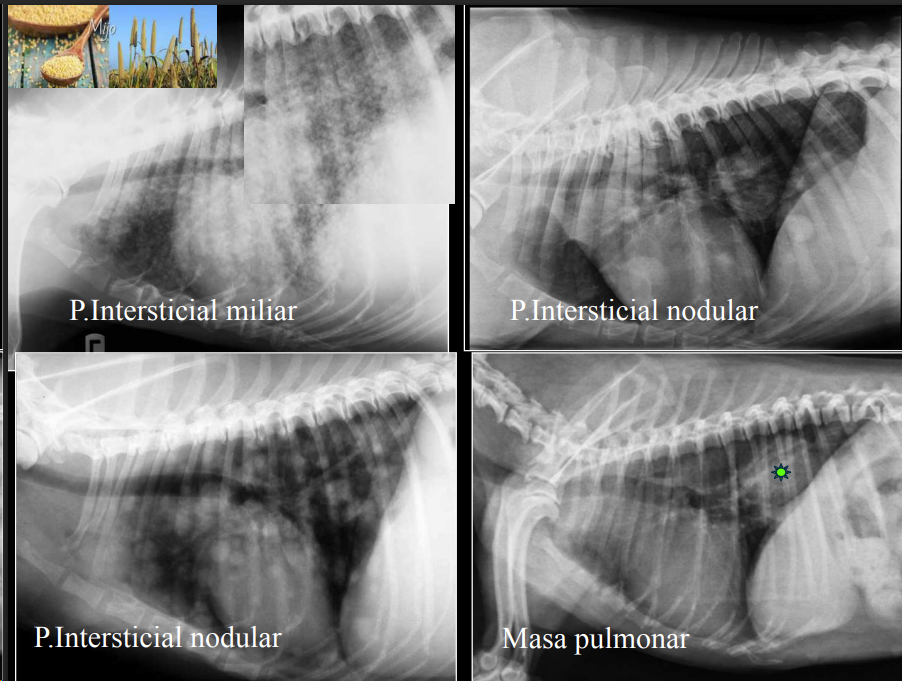

Nodular/Estructurado:

- Opacidades redondeadas (“miliar”, “nodular”, “masa”). A veces se puede confundir el patron miliar con calcificaciones (ocurren en pacientes mayores) pero estos tienen una mayor cantidad de radioopacidad al ser casi hueso.

- No confundir con patron miliar con los vasos transversales. Mas comunes cerca de la aorta, menos comun en la periferia del pulmon.

- Causas: metástasis, abscesos, tumores, granulomas.